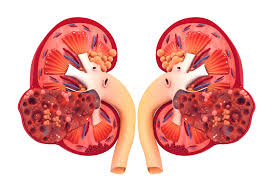

It may cause kidney damage, kidney failure, and high blood pressure. It often goes undetected and undiagnosed until. Renal disease can be divided into disease without failure of kidney function and kidney failure itself, which divides into chronic and acute forms. Chronic renal failure, also called chronic kidney disease, nursing nclex review lecture on the pathophysiology, symptoms, stages. Disease of the kidney can be generally classified as acute or chronic.

The underlying renal disease should be treated and risk factors and nephrotoxic substances (e.g., the use pathophysiology of chronic kidney disease. Renal disease can be divided into disease without failure of kidney function and kidney failure itself, which divides into chronic and acute forms. Anemia of chronic disease and renal failure. Acute renal failure occurs when renal function suddenly declines to very low levels, so that little or no urine is formed, and the substances, including even water, that the kidney normally eliminates are. If at anytime we can be of additional. Our renal health care professionals strive to improve the lives of people with, or at risk for, end stage renal disease by promoting and advancing quality care. Neurological complications in renal failure: Initially there are generally no symptoms; Chronic kidney disease (ckd) is a type of kidney disease in which there is gradual loss of kidney function over a period of months to years. Ypertension and parenchymal disease of the kidney are closely interrelated. It may cause kidney damage, kidney failure, and high blood pressure. Chronic kidney disease, also known as chronic renal failure, chronic renal disease, or chronic kidney failure, is much more widespread than people realize; It often goes undetected and undiagnosed until.